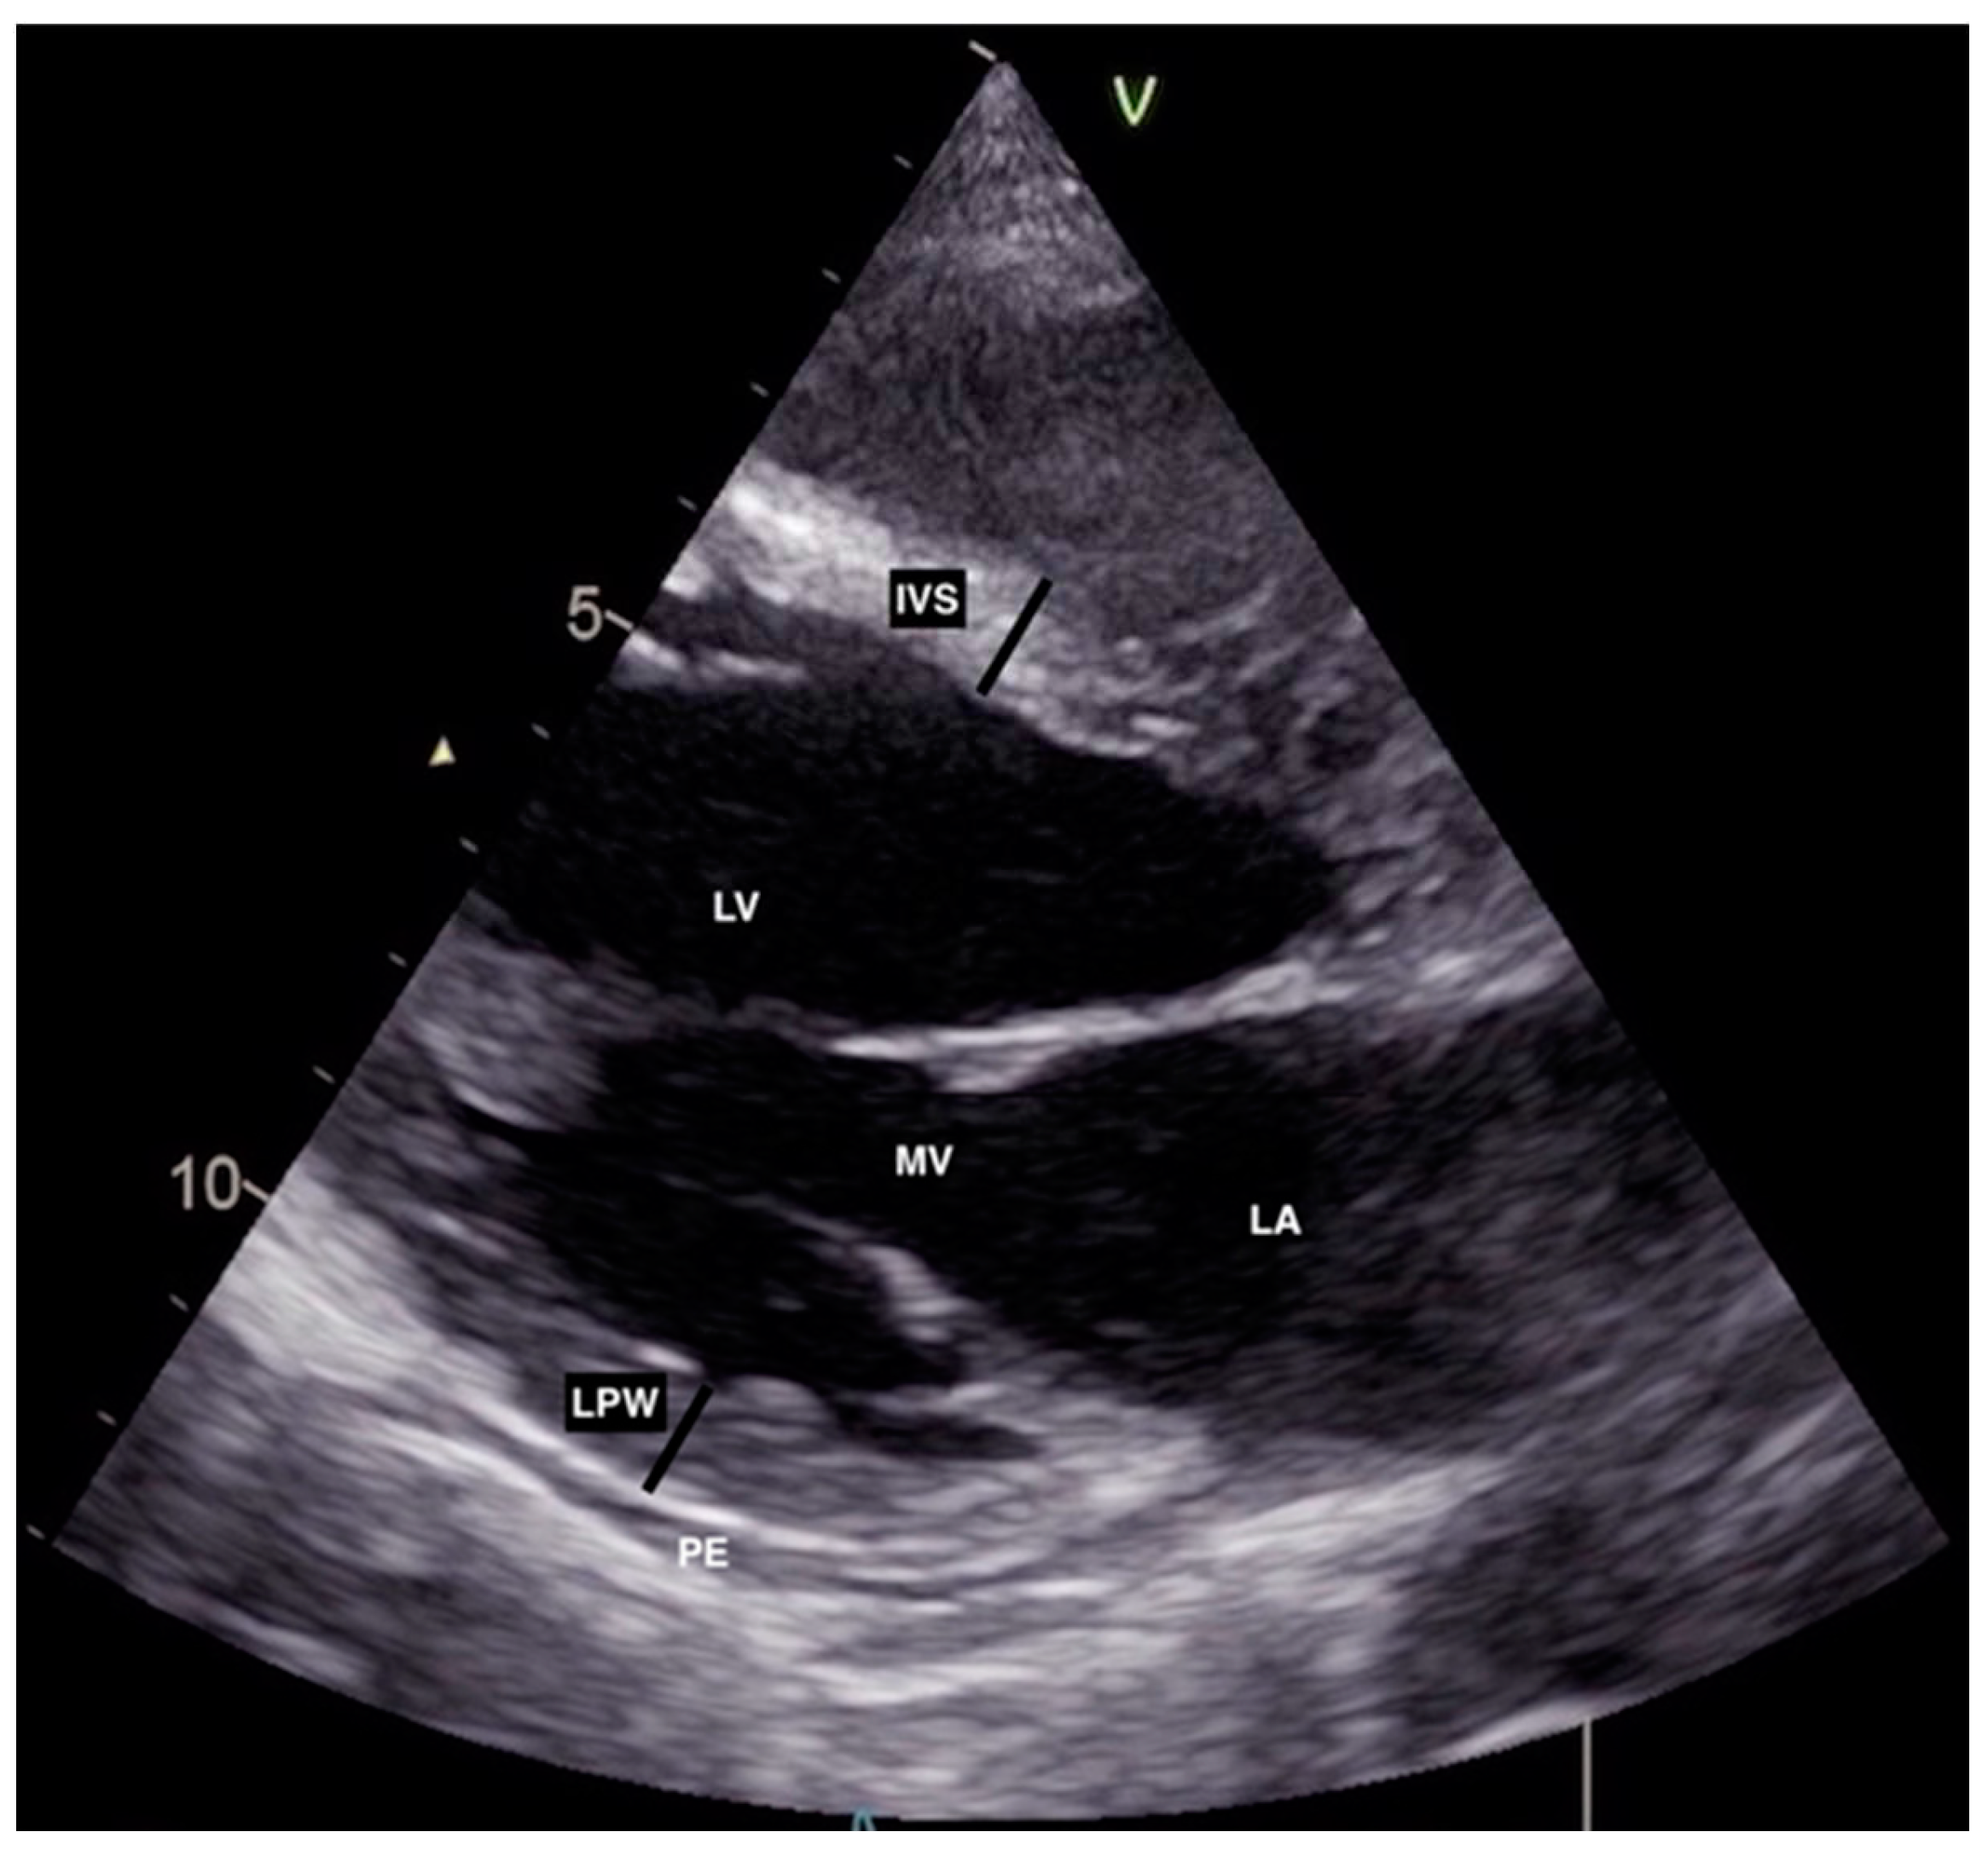

2. Case Description